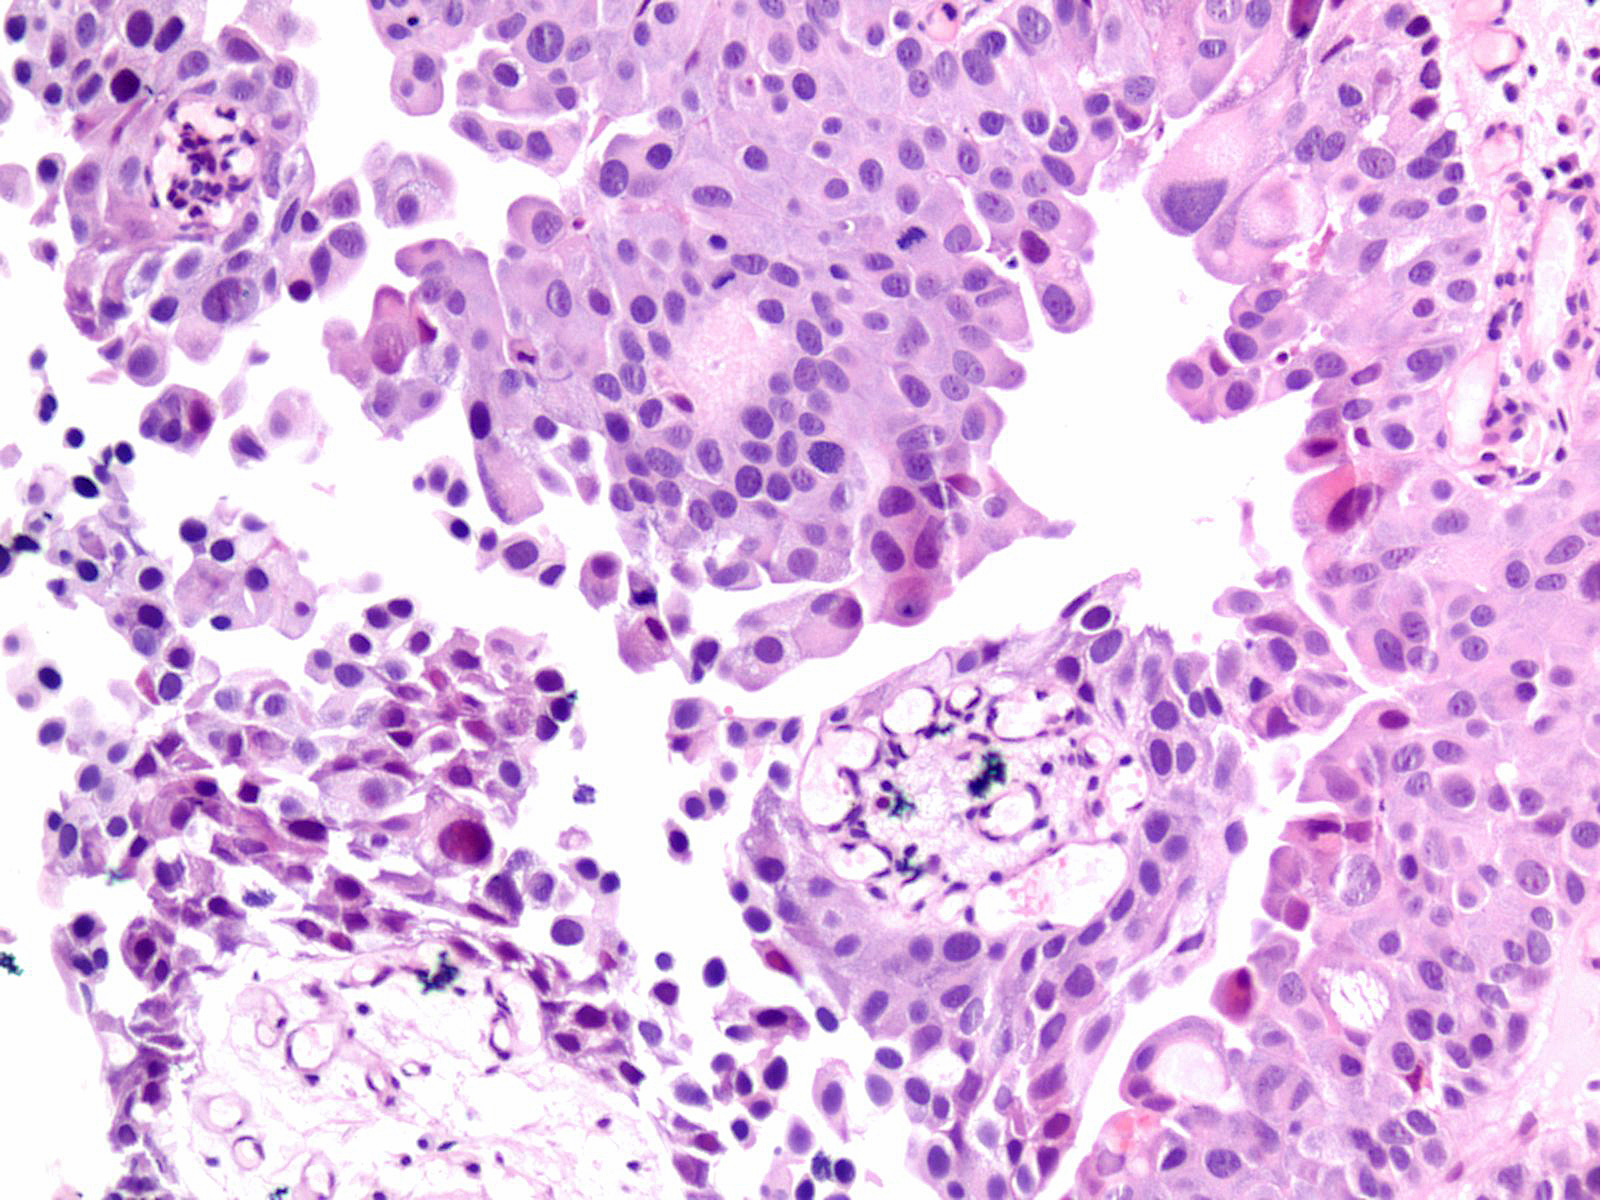

Consensus grade: High-grade papillary urothelial carcinoma (HG-PUC)

Lesion shows marked variation in nuclear size, shape and chromatin. Architecturally, cells appear loosely cohesive and the epithelium is disorganized. Mitotic figures are seen.